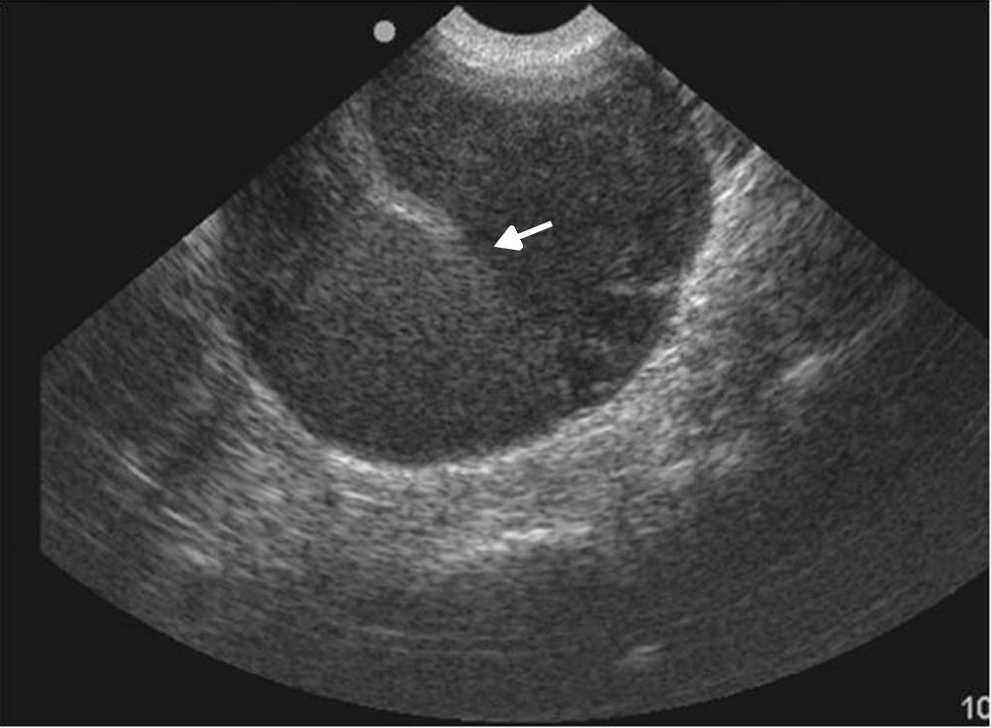

Las principales causas de esta dolencia son los quistes de ovario simples o hemorr??gicos, los embarazos ect??picos, las enfermedades inflamatorias pelvianas, las torsiones de ovario y otras patolog??as, muchas de las cuales tienen caracter??sticas ecogr??ficas propias que permiten su diagn??stico5 (figs. 1-3).

La ecograf??a determina la naturaleza s??lida o qu??stica de las masas anexiales, la presencia de septos o elementos s??lidos, y su vascularizaci??n con la exploraci??n Doppler (fig. 4). Estos hallazgos ayudan a determinar la benignidad o malignidad de la masa5,10.